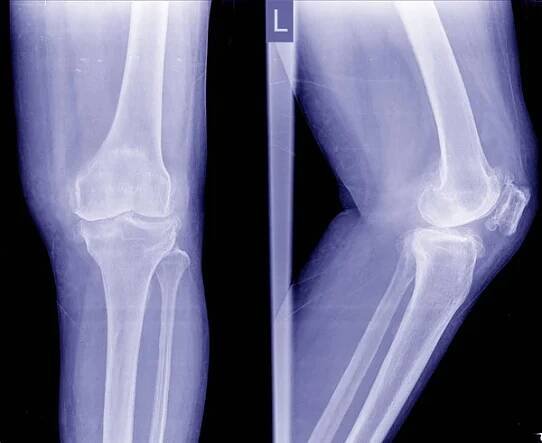

Osteoartróza (Oa) koleno. Film rentgenové Apand boční pohled kolena ukazují úzká kloubní štěrbiny, subchondrální skleróza, osteofytů (spur), zánět kolenního kloubu. — Stock obrázek